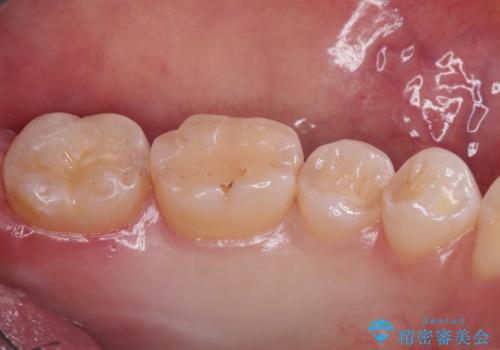

- 一番奥の歯の古い材料が劣化してしまい、欠けて黒くなっているのが気になるとの事でした。

詰め物のやりかえを提案したところ、セラミックインレーをご希望されたのでセラミックインレーにて治療をすることにしました。

古い材料と虫歯を除去して、型取りをしました。

適合も非常に良く、綺麗になりました。